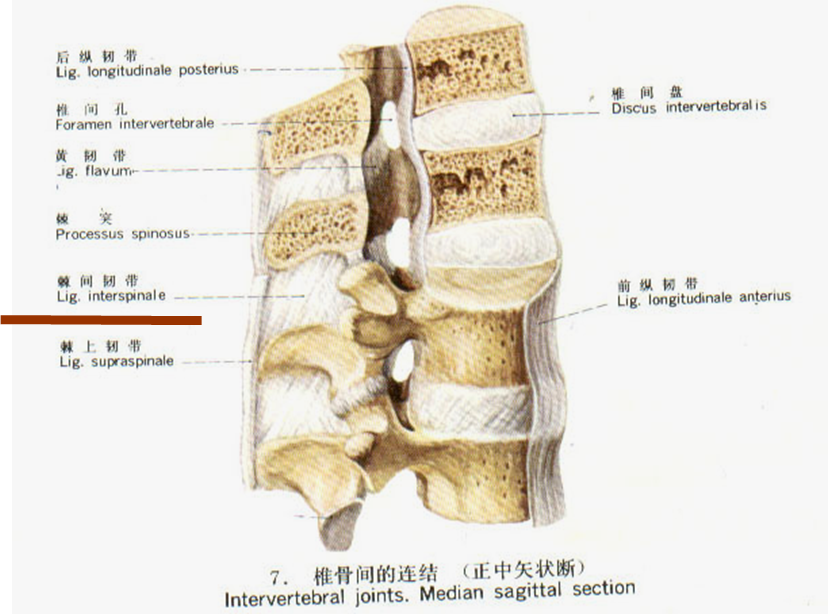

棘上韧带

是由腰背筋膜、背阔肌、多裂肌的延伸(腱膜)部分组成,分3层,深层连接相邻2个棘突,且与棘间韧带交织在一起;中层跨越2~3个棘突;浅层跨越3~4个棘突。

作用:与黄韧带一起在棘间韧带帮助下限制脊柱过度前屈。

棘间韧带

位于相邻的两个棘突之间的较深处,其薄而无力,不如棘上韧带坚韧。腰1~腰3的棘间韧带分为前部、前中部、中部和后中部四部分,腰4、腰5~骶1的棘间韧带只有前、中、后三部分,各部分相互交叉排列。

棘间韧带有要腰神经后支分布,和棘上韧带一起限制脊柱过度前屈的作用。